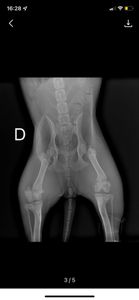

Segundo exames de Raio X, o atropelamento causou 2 fraturas na regiao de pelve e necessita de intervencao cirurgica com custo aproximado em R$3900 reais, que é um custo bastante elevado e precisamos do apoio e da colcaboracao de todos para não deixa-lá morrer, pois ela não consegue se colocar de pé devido a gravidade das fraturas.